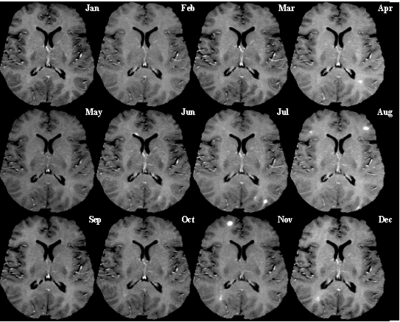

- Magnetic resonance imaging (MRI) and magnetic resonance spectroscopy (MRS) of the brain and spine is often used during the diagnostic process. MRI shows areas of demyelination ( lesions) as bright spots on the image. Gadolinium can be administered intravenously to highlight active plaques and, by elimination, demonstrate the existence of historical lesions not associated with clinical symptoms. This can provide the evidence of chronic disease needed for a definitive diagnosis of MS.